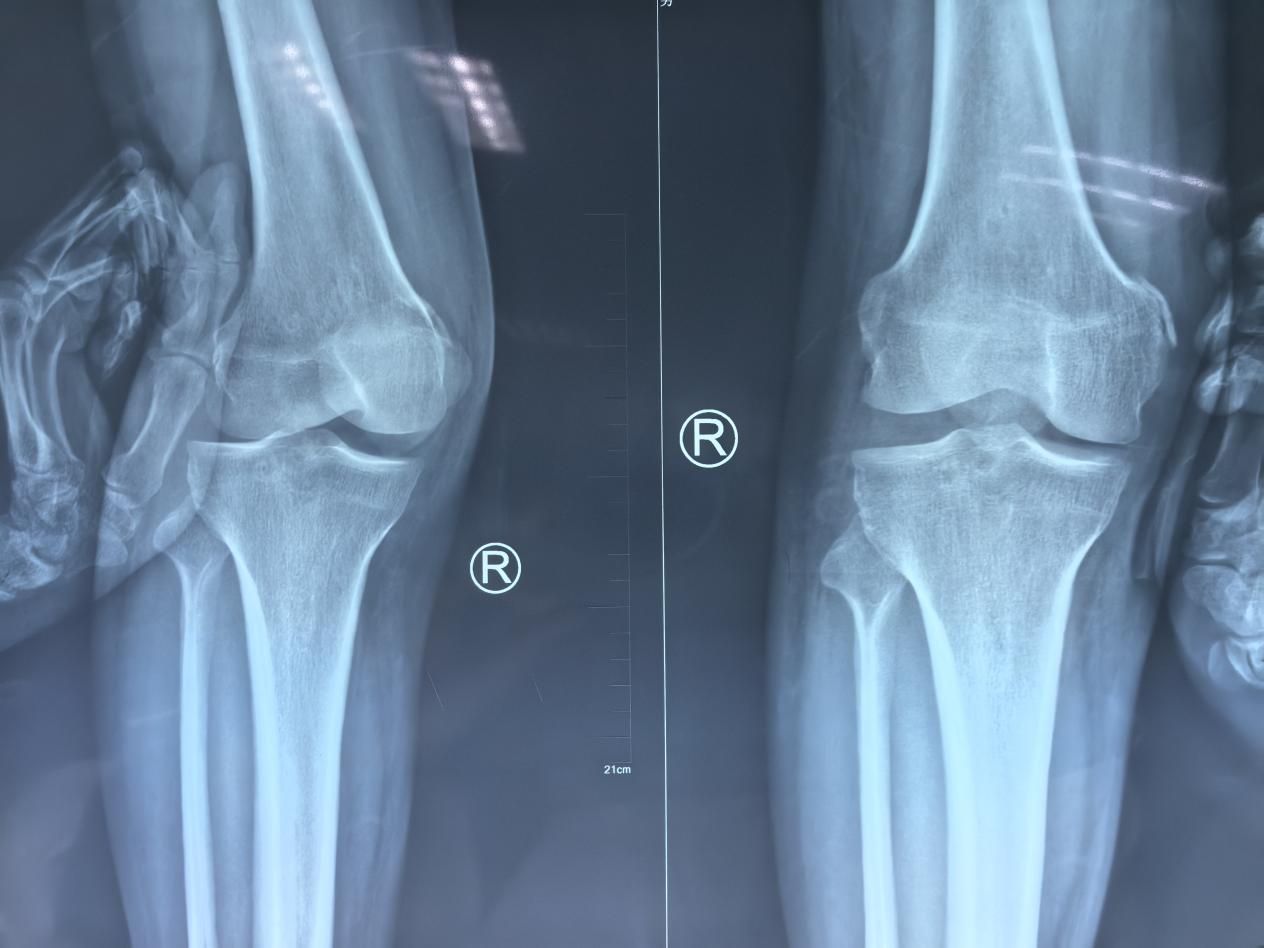

首例患者因车祸导致右膝关节多发韧带损伤,诊断为后交叉韧带断裂合并外侧副韧带断裂。马瑞医生凭借丰富的关节镜手术经验,为患者实施了“右膝关节镜下后交叉韧带重建术+外侧副韧带重建术”。手术过程顺利,仅用时2小时便完成了这一技术难度较高的复合韧带重建,展现了团队在运动损伤修复领域的精湛技艺。